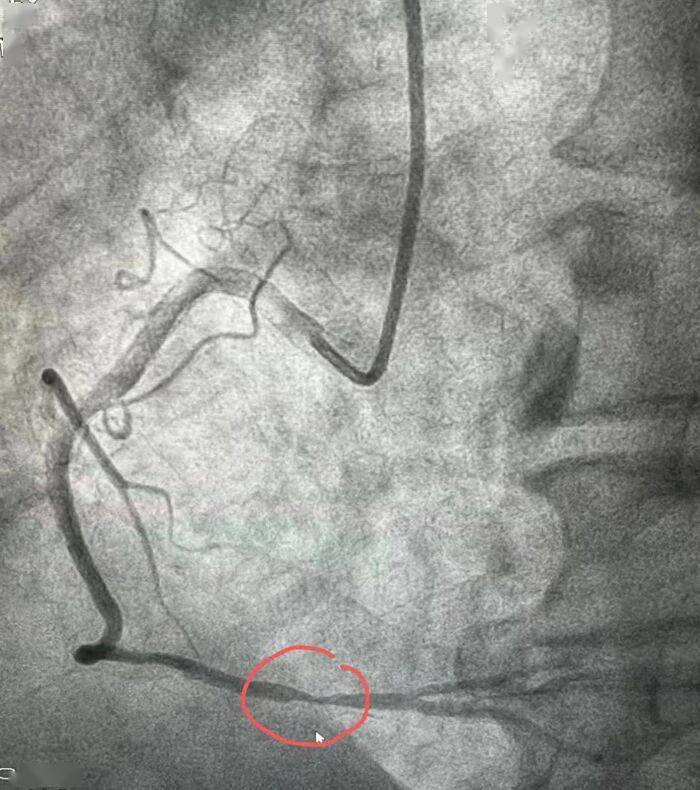

血管造影,造影发现脑血管病变比心脏更为严重,双侧椎动脉中左侧为闭塞

图片尺寸700x790